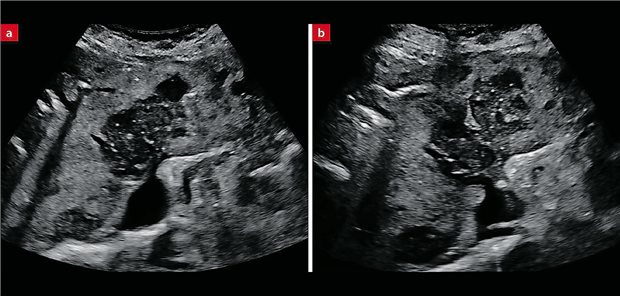

Aus dem sonografischen Nachweis von Läsionen der Leber ergibt sich oft der Verdacht auf ein fortgeschrittenes Tumorleiden. Später kann es jedoch auch zu einer völlig anderen Diagnose kommen.